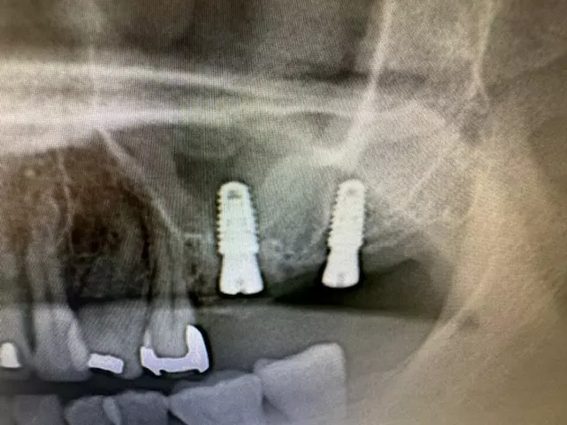

| 主訴 | インプラント 左上6番7番部 インプラント埋入 |

| 治療内容 | 左上6番7番部インプラント埋入。 左上6番部 上顎洞まで約1.5㎜。 左上6番 抜歯即時埋入。 左上7番 もともと歯が無かったため、通常埋入。 |

上顎洞へ突き抜けているように見えますが、抜歯窩への埋入のため、実際は抜けていません。